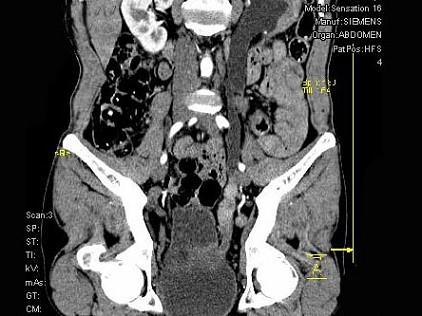

问题 男,46岁,无痛性血尿2个月,CT扫描如图所示,应诊断为 ( )

选项 A、左侧输尿管结石 B、左侧输尿管血块 C、左侧输尿管炎 D、左侧输尿管癌 E、左侧输尿管结核

答案 D